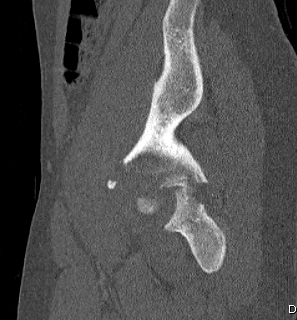

1. Posterior Wall

- often associated with posterior dislocation

- may be in one or many pieces

- may have marginal impaction fracture

2. Posterior Column

- whole posterior column separated in one piece

- fracture greater sciatic notch

- through inferior acetabulum

- into obturator foramen

- through inferior pubic rami